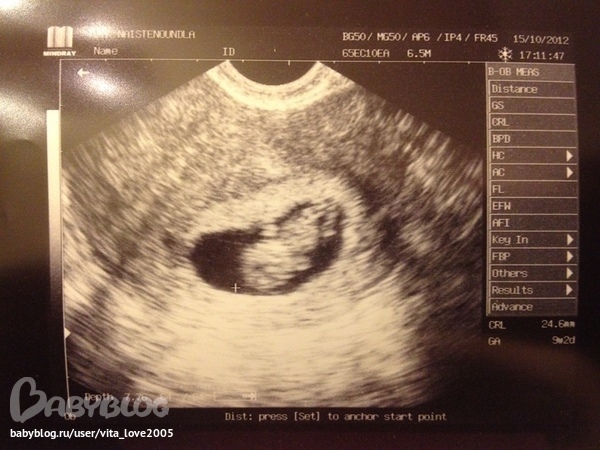

Безумно ждала этого дня, переживала, хотела наконец-то увидеть наше чудо маленькое!!!!!))) Акушерка очень хорошая, она знала русский язык, и все очень конкретно объясняла,отвечала на все вопросы, и сделала узи, хотя должна была только послушать сердце. Она посматрел по карте, что у меня был выкидышь, и видела как я волновалась. Она долго показывала мне моего малыша, и у меня сердце замирало при каждом движение ножек и махания ручек, сердечко стучало очень быстро

!!!! Акушерка ждала пока я насмотрюсь и пойму что все впорядке, и сама улыбалась так приятно. когда она закончила я поняла что глаза все в слезах........ Наше солнышко 2,5 см, полнастью соответсвует сроку вплоть до дней 9 недель и 2 дня!)))))))))))

Ну и вот наше маленьое чудо!!)))) Надеюсь поймете где что!)))